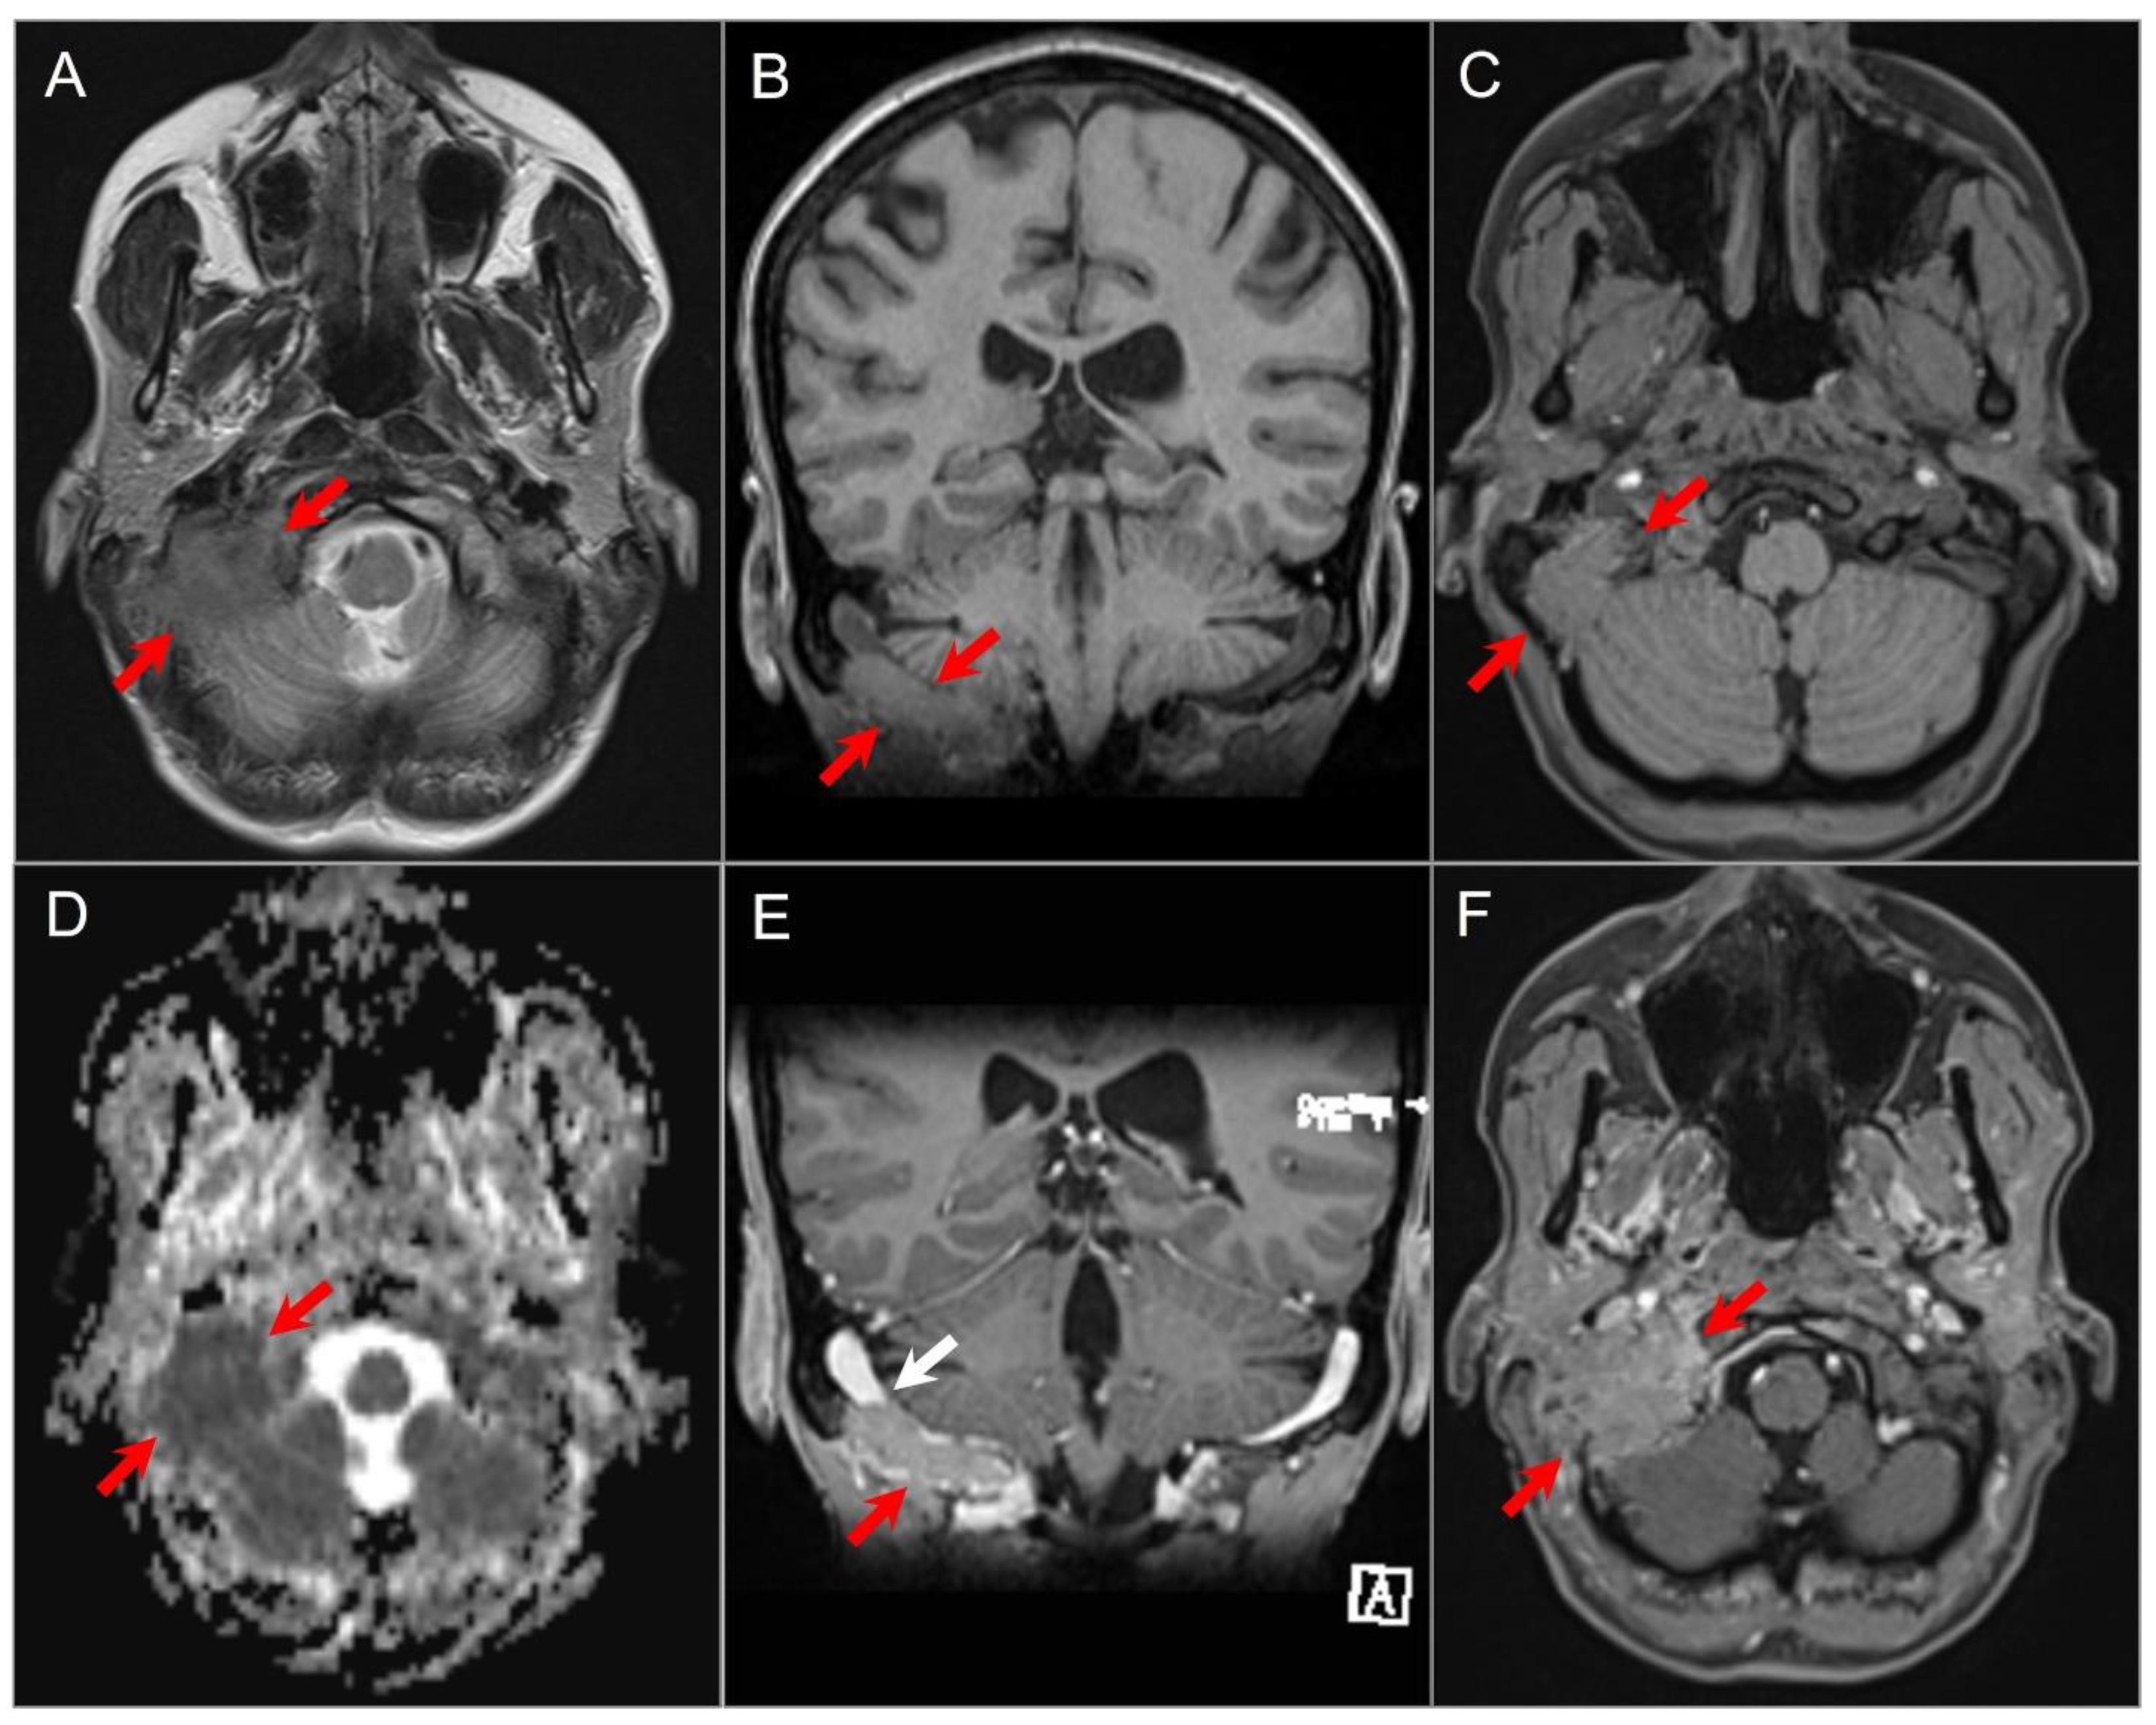

4.4.5. Paraganglioma